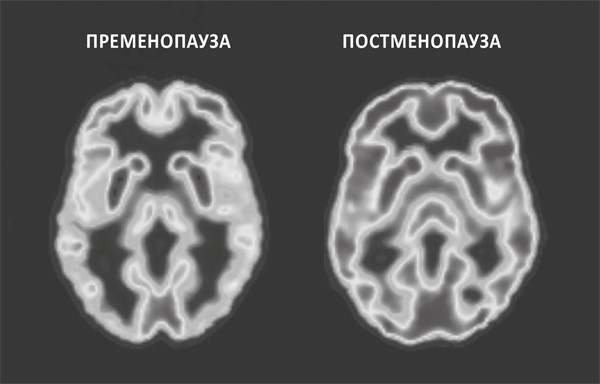

Это хорошо видно на приведенных ниже снимках со сканера. Слева показана метаболическая активность мозга женщины, еще не имеющей признаков менопаузы, т. е. на этапе пременопаузы. На правом снимке – мозг женщины в постменопаузе. Насыщенность серого оттенка отражает степень активности: чем темнее, тем ниже. Снимок мозга в постменопаузе в целом выглядит темнее, а это значит, что его метаболические процессы протекают значительно менее активно, чем в пременопаузе. И это не единичный случай. Снимок, можно сказать, «усредненный». По нашим наблюдениям, в некоторых случаях уровень активности мозга снижается на целых 30 %. Тревожно, что такие же результаты были замечены у женщин уже незадолго до наступления менопаузы. А вот у мужчин того же возраста отмечались минимальные изменения, а во многих случаях – вообще никаких.

РИСУНОК 1. МЕНОПАУЗА: АКТИВНОСТЬ МОЗГА ДО И ПОСЛЕ